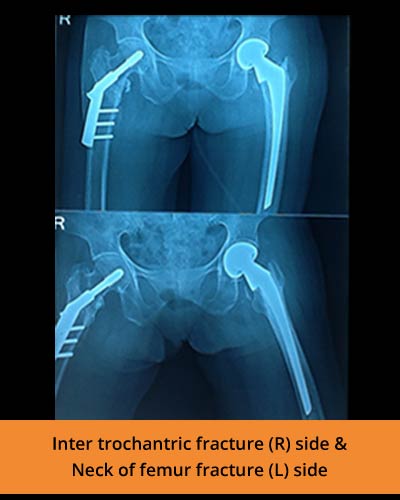

🩺 Fracture management and trauma care

At TPN Hospitals — the top orthopaedic hospital in Erode — our specialists use advanced methods to perform limb lengthening, correct deformities, and treat complex fractures with precision and care

Addressing infected non-union of long bones, osteomyelitis, and polytrauma cases with specialized care.